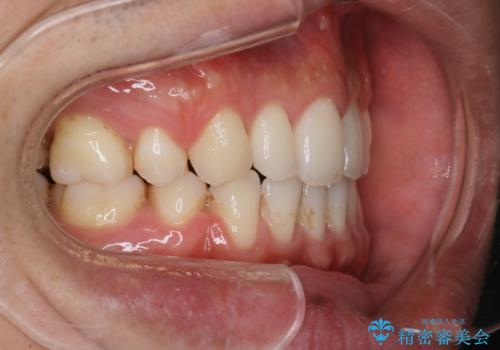

前歯の隙間を閉じたい 口元も下げたい ハーフリンガルによる抜歯矯正

- 上の前歯の隙間と口元を下げたとのことで来院されました。

上顎正中離開と、口唇の突出感がありました。

上下左右の歯を1本ずつ抜歯しして、上顎の前歯を後方に移動させるのと、正中の隙間を閉じる計画としました。

抜歯をせず上顎の正中離開のみの矯正もできましたが、患者様と相談して口元の改善も同時に行うために抜歯矯正の計画としました。